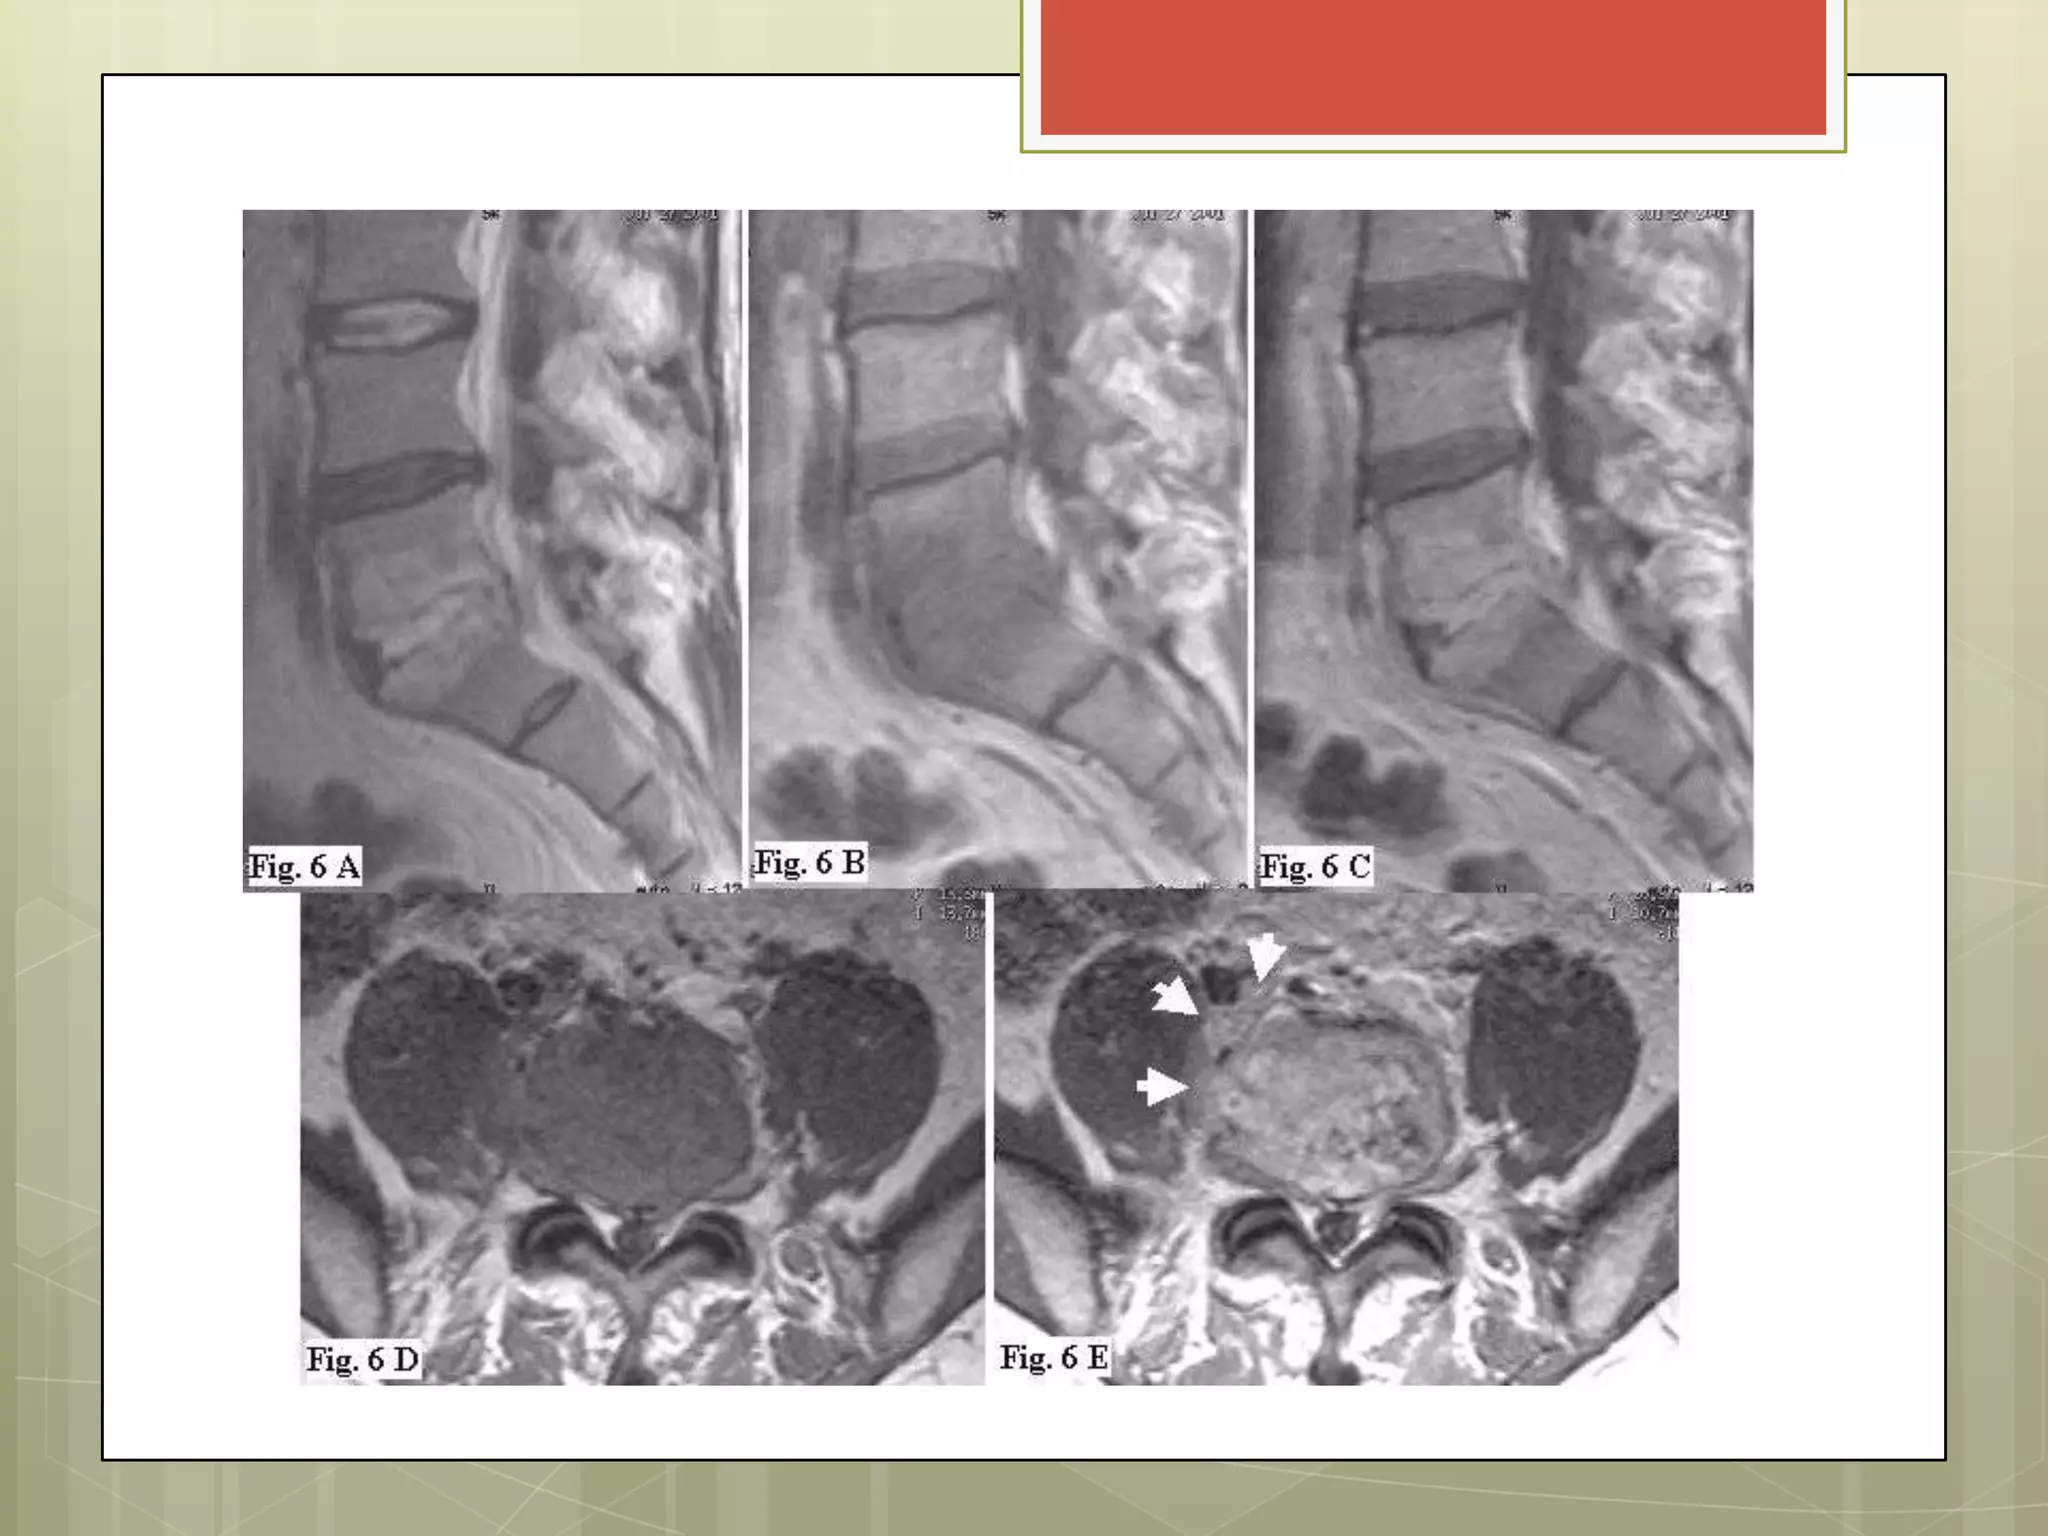

SD DE CANAL ESTRECHO LUMBAR

• ↓ calibre normal del canal vertebral

• Congénita: RARA

Degenerativa artrósica: FRECUENTE (sobretodo L4, L5)

• Síntomas cuando:

-Degeneración discal

-Espondilolistesis

-Hipertrofia de Facetas

-Lamina Ligamentos

ETIOPATOGENIA

Estenosis de saco dural→

compresión de las raíces nerviosas

Movimiento de Columna→

Raíces son comprimidas →

↓ irrigación y compromiso de función.

ESTENOSIS FORAMINAL

Estrechamiento de los agujeros de conjugación por los que

salen desde la columna las raíces de los nervios raquídeos.

Mas comunes lumbares y cervicales.

TAC nivel de L5 -S1 mostrando un disco intervertebral y saco

dural normales, pero con un estrechamiento del foramen lateral

derecho (triángulo). La articulación sacroilíaca derecha

(cabezas de flecha) tiene evidencia de proceso artrítico leve.